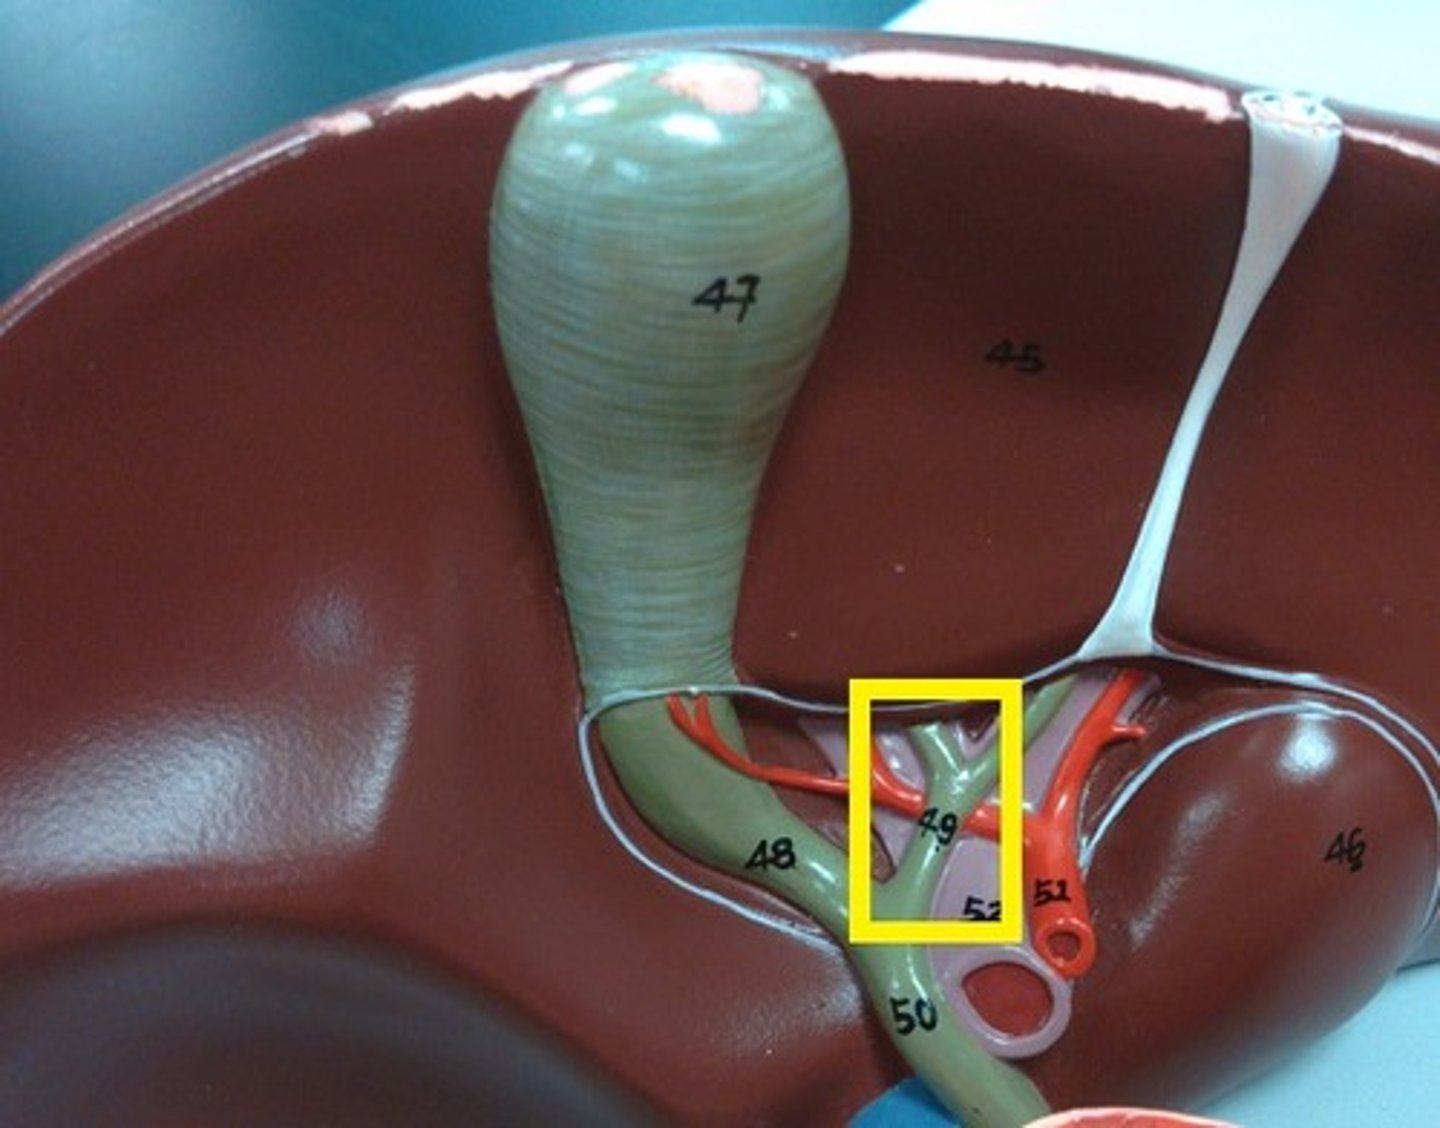

hepatoduodenal ligament

portal triad

what is in this structure

porta hepatis

where the blood and lymph vessels, bile ducts, and nerves enter and leave the liver

hepatic artery proper

right hepatic artery

left hepatic artery

cystic artery

common bile duct

common hepatic duct

cystic duct

hepatic portal vein